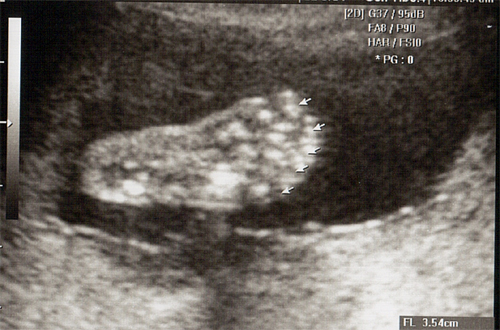

강아 ^^ 21주 강이의 정밀 초음파를 봤어 일반 초음파 보다는 더 정밀하게 나오더라구 엄청 커버린 강이가 한눈에 보이지 않을정도로 이제는 초음파 기계가 작아 보이더라..

암튼 건강하고 아무 이상없이 잘 자라주고있는 강이를 보면 아빠를 힘이나고 더욱 열심히 해야 겠다는 생각이 든단다..